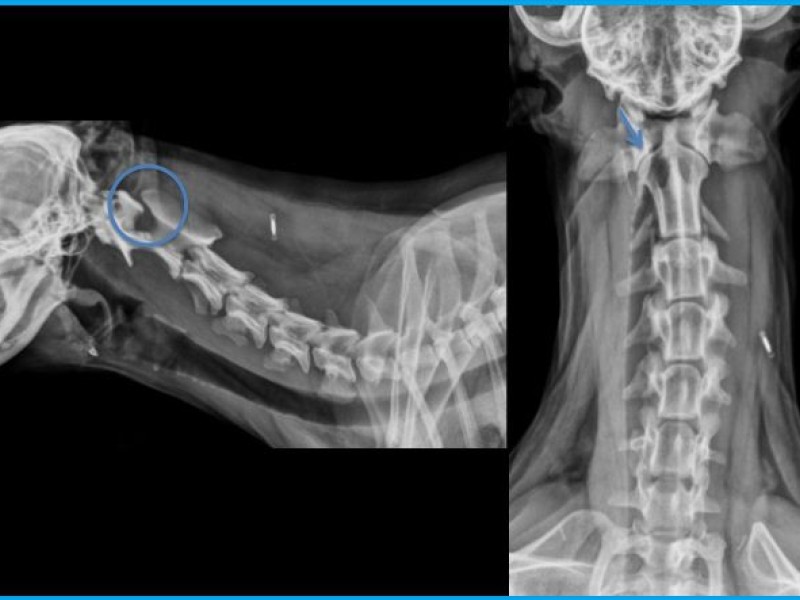

A cervical lesion is suspected and cervical radiographs taken.

Do you see abnormalities? Can these abnormalities explain the clinical signs?

There is a marked increase in space between the dorsal lamina of C2 and the dorsal neural arch of C1. On the VD view, the dens of the axis is hypoplastic. The facet joints between C1 and C2 are enlarged and uneven. There are step defects visible along both joint margins with a loss of alignment. The intervertebral disc space between C2 and C3 is reduced compared to adjacent spaces.

Assumptions: Atlanto-axial subluxation and suspected herniated disc C2C3.

Both lesions may explain the clinical signs.